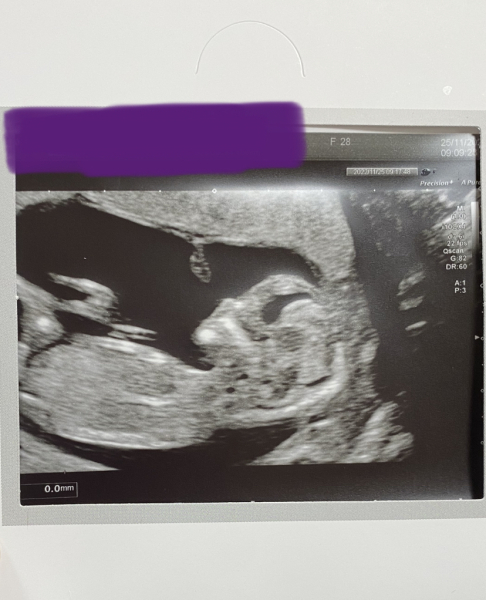

My scan this morning went perfectly and I need not have worried about the previous small measurements. Everything looked great and baby is now measuring slightly ahead of what I thought at 12+6! 🥰😍🤩

PS. any gender theorists out there? I would love a guess. I had a sneak peek but am pretty sure I contaminated my results so can't 100% trust the boy result! 🙈

@B1993 Yippee! That's a great picture - hope it eases the worry a bit. NO idea wrt sex - I had umpteen scans with my little girl, still none the wiser when she popped out...